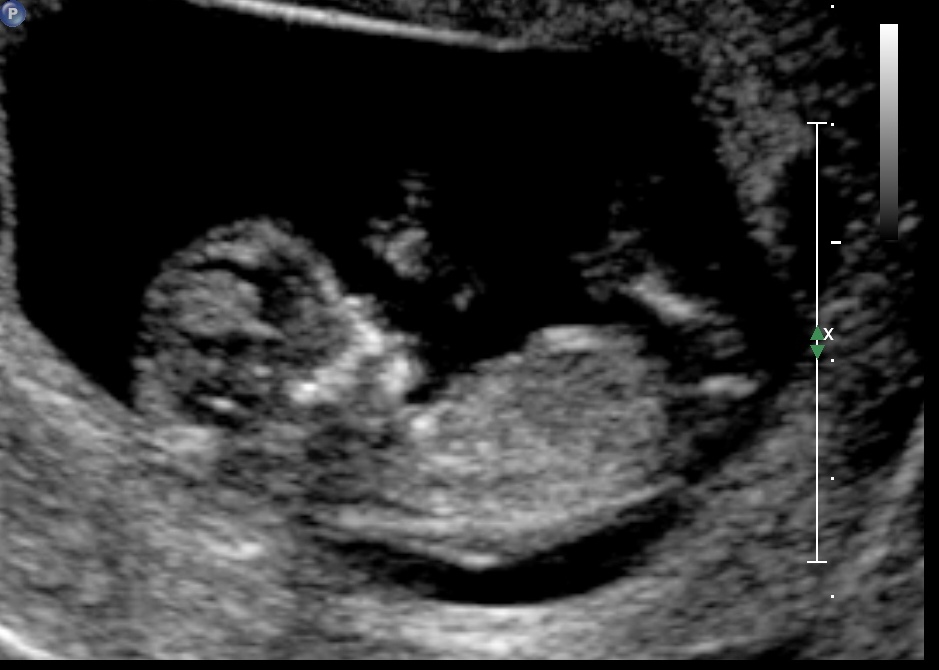

After 6 boys we are really hoping for a girl. Can any one please take a guess. :-)

Attachment 21857

Definitely looks girly :) excited for you!

looks girly!

Leaning pink

Looks girly- good luck!